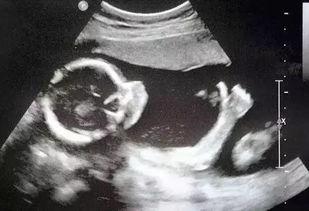

据网友爆料,这段视频是在某家医院的B超室内拍摄的。视频中,一名身穿白大褂的医生正在为一位孕妇进行B超检查。令人意想不到的是,这段视频竟然被泄露到了网上。视频中,医生和孕妇的动作十分亲密,引发了网友们的广泛关注。